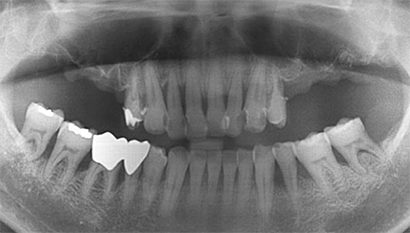

W Dental Clinic Before & After

치료 전후사진

Before